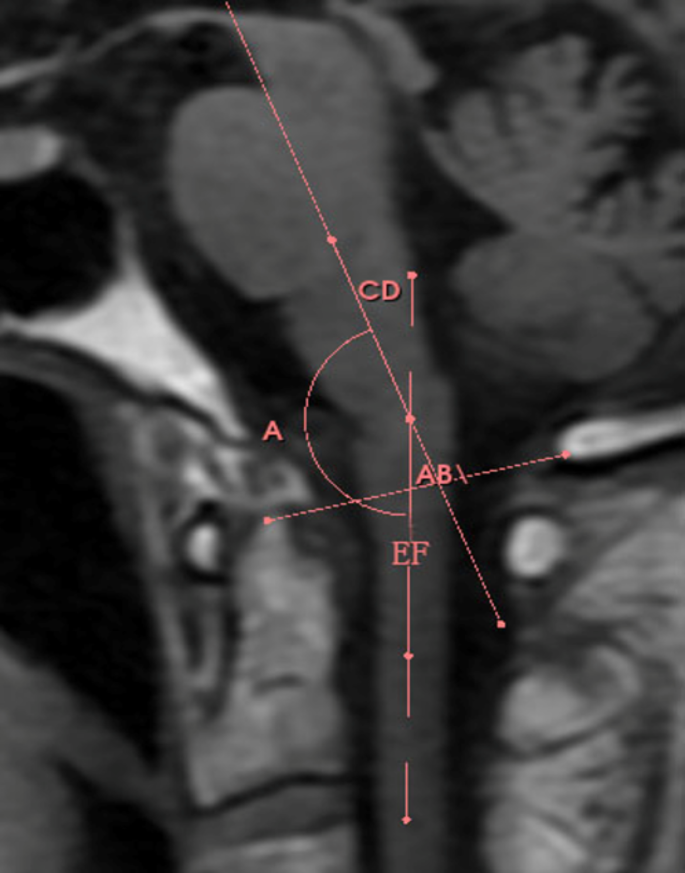

Measurement of brainstem and spinal cord angle

The angle between the brainstem and spinal cord was measured as the intersection angle of the brainstem and spinal cord middle tangents passing through the plane of the cerebral aqueduct (Fig. 3), where AB is the line along the foramen magnum, CD is the midline of the brainstem, EF is the midline of the spinal cord, and ∠A is the angle formed by the intersection of lines CD and EF.